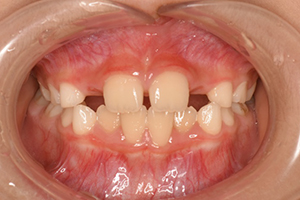

歯並びが気になる

レントゲン写真 治療内容・期間 7歳の時に、歯並びが気になるとのことでいらっしゃいました。最初の状態が左の写真です下の前歯は叢生です。上の前歯は、オレンジの矢印のところに側切歯が入るはずなのですが、隙間が小さくて出てこられない状態でした。さらにその後ろの犬歯も、顎の中で重なり合っていて出にくくなっています。 7歳の時...